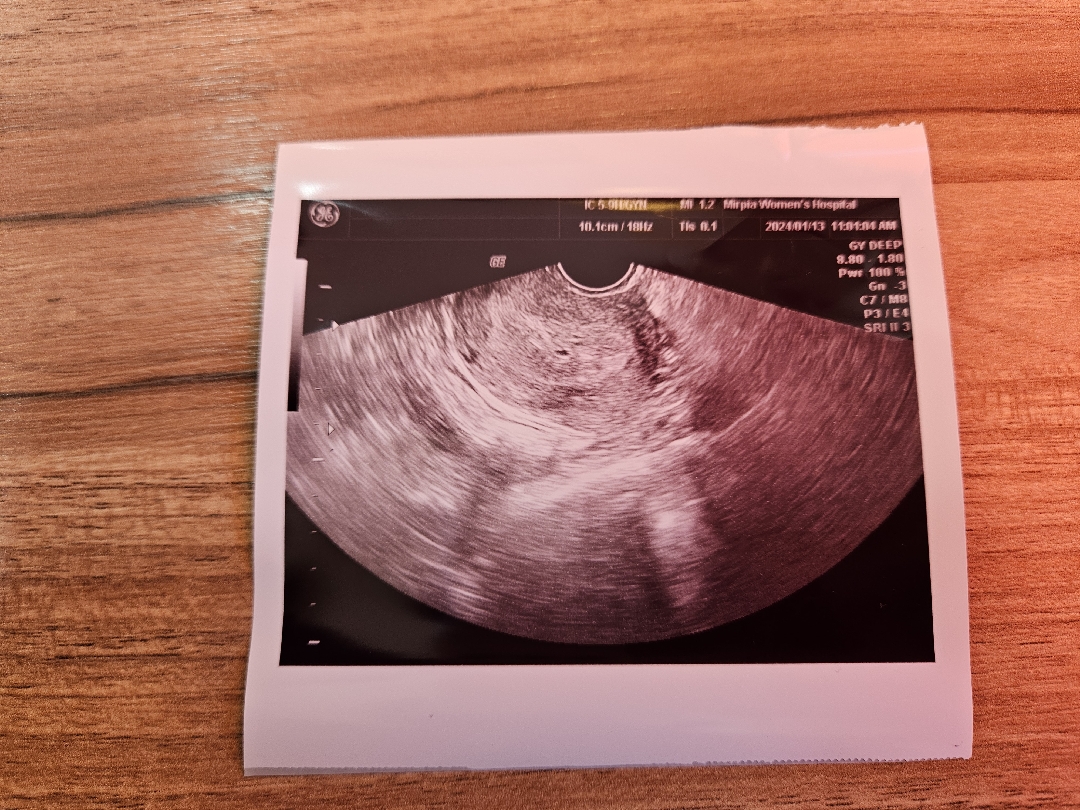

5주5일 드디어아기집봤어요

5주 1일차부터 출혈이있었고 5주 3일차 빨간피를 보게되어 병원에 다녀왔어요 이때 아기집은 안보이고 피검수치는 2288이었습니다 더블링이 잘되고있어서 걱정말고 2일후 방문하라고 하셨지만 수치에 비해 아기집이 안보여서 너무 힘들더라구요... 그런데 드디어 오늘 ! 작지만 소중한 아기집을 봤습니다 제가 생리주기는 일정하지만 배란이 늦는 편이라는 것을 산부인과에서 들어서 알고있었지만 수정이 늦게 된것 같더라구요 ㅎㅎ 그간 너무 마음 졸였던게 한시름 놔졌어요 남편도 내색은 안했지만 마음을 많이 졸였나봐요 검진 받고 배고파서 간 해장국집에서 손잡고 같이 울었네요 꼭꼭아 다음주에 더 커서 만나자 ♡♡ 주수에 비해 아기집이 안보여서 걱정많으신 분들이 계실것같아 도움이 되고자 글씁니다. 다들 임신기간동안 건강하시길 기도합니다🙏